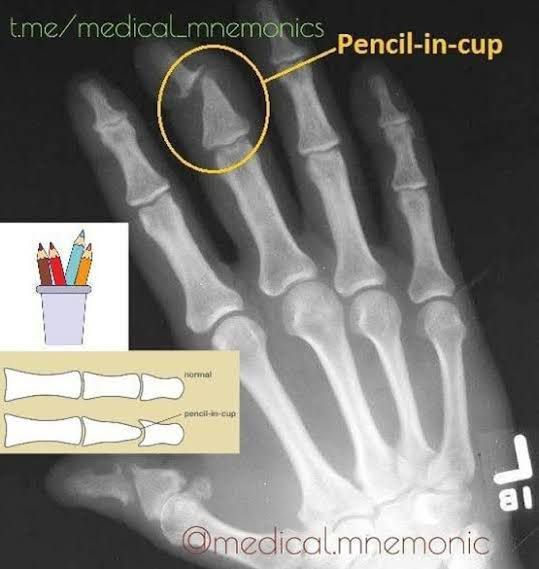

Pencil-in-cup deformity is a rare bone and joint condition usually associated with a severe form of arthritis called arthritis mutilans. On a scan, the affected bone may seem pointed, like a sharpened pencil, and it may wear away at a nearby surface, which becomes cup-like.